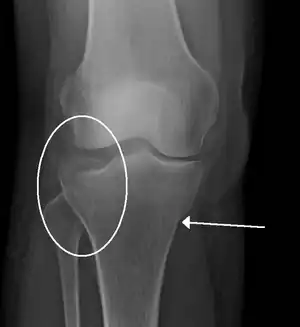

A severe tibial plateau fracture with an associated fibular head fracture

A tibial plateau fracture is a break of the upper part of the tibia (shinbone) that involves the knee joint.[2] Symptoms include pain, swelling, and a decreased ability to move the knee.[2] People are generally unable to walk.[3] Complication may include injury to the artery or nerve, arthritis, and compartment syndrome.[2]